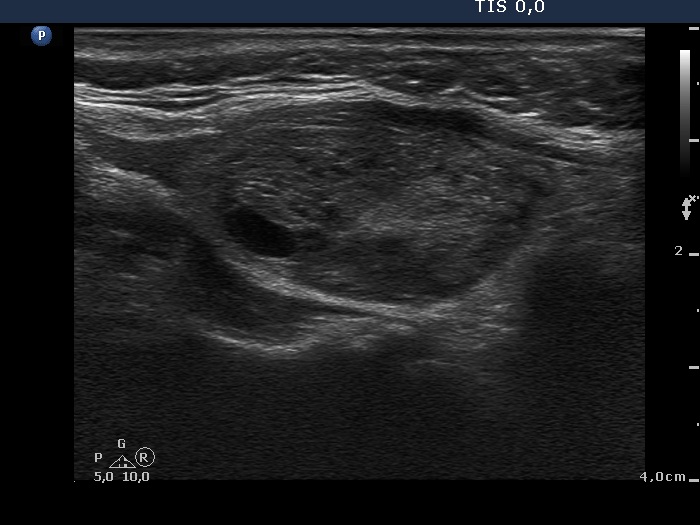

Ethanol sclerotherapy: toxic nodules - Case 2

First session of repeated therapy (ultrasonographic picture 2)

Right lobe, longitudinal scan.